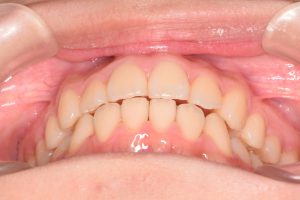

この患者さんは、初診時12才女性。

「上の前歯の中心がずれている」

「全体的に歯並びが良くないのが気になる」

ということで来院されました。

保定開始時(2025年1月)の写真です。

正面